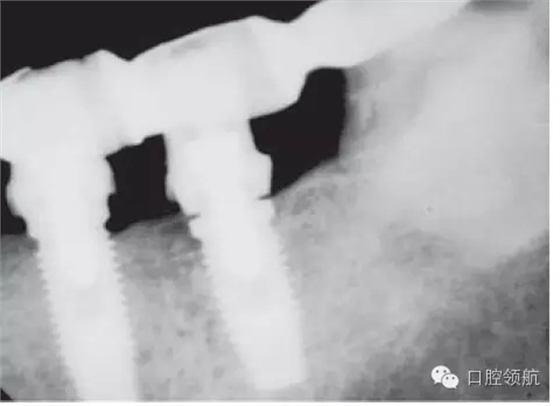

另外一個方面,深的袖口將妨礙修復(fù)體完全就位(圖9.26)。通常可以通過放射學(xué)檢查,確認(rèn)修復(fù)部件的就位情況,包括種植體與基臺的連接部分。即使是內(nèi)連接,轉(zhuǎn)移體或者其他修復(fù)部件也會因深袖口而不能就位。以下技術(shù)可以用于解決這些問題:可以在局部麻醉下,插入喇叭狀或者外展的基臺,以非手術(shù)的方式擴大袖口(圖9.27 a,b),然后再通過放射學(xué)檢查確定部件的完全就位。組織會受壓發(fā)白,15分鐘后,軟組織將會擴張,以允許理想修復(fù)部件的就位,這樣治療將得以繼續(xù)。有時,需要在鄰面做兩個小切口,以緩解袖口軟組織張力(圖9.28 a,b)。通常不需要縫合。一旦袖口組織塑形完成,可運用最佳塑形的臨時(圖9.29)或最終部件(圖9.30),來維持理想的軟組織外形。

圖9.26 放射學(xué)影像顯示,在外六角連接的種植體上,基臺沒有完全就位。